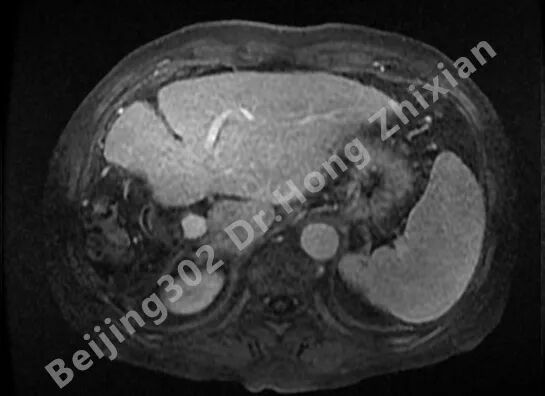

病例简介